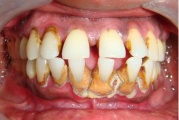

Krooniline parodontiit

Krooniline parodontiit on mikroobide poolt põhjustatud hammaste tugikudede põletik, mille tulemusena tekib progresseeruv alveolaarluu (nähtav röntgenograamil) ja periodontaalligamendi destruktsioon, igemetaskute moodustumine, igeme retsessioon või mõlemad kahjustused kombineeritult. Loe edasi »

Sümptomid:

- igemed veritsevad (19)

- igemed punetavad (21)

- ige on paistes (mädapunn)

- igemed on tursunud/vohavad (17)

- igemed on valulikud (19)

- igemepiir on taandunud (3)

- luu destruktsioon (5)

- puudulik suuhügieen (5)

- igemepealne hambakivi (5)

- igemealune hambakivi (4)

- vahed hammaste vahel (5)